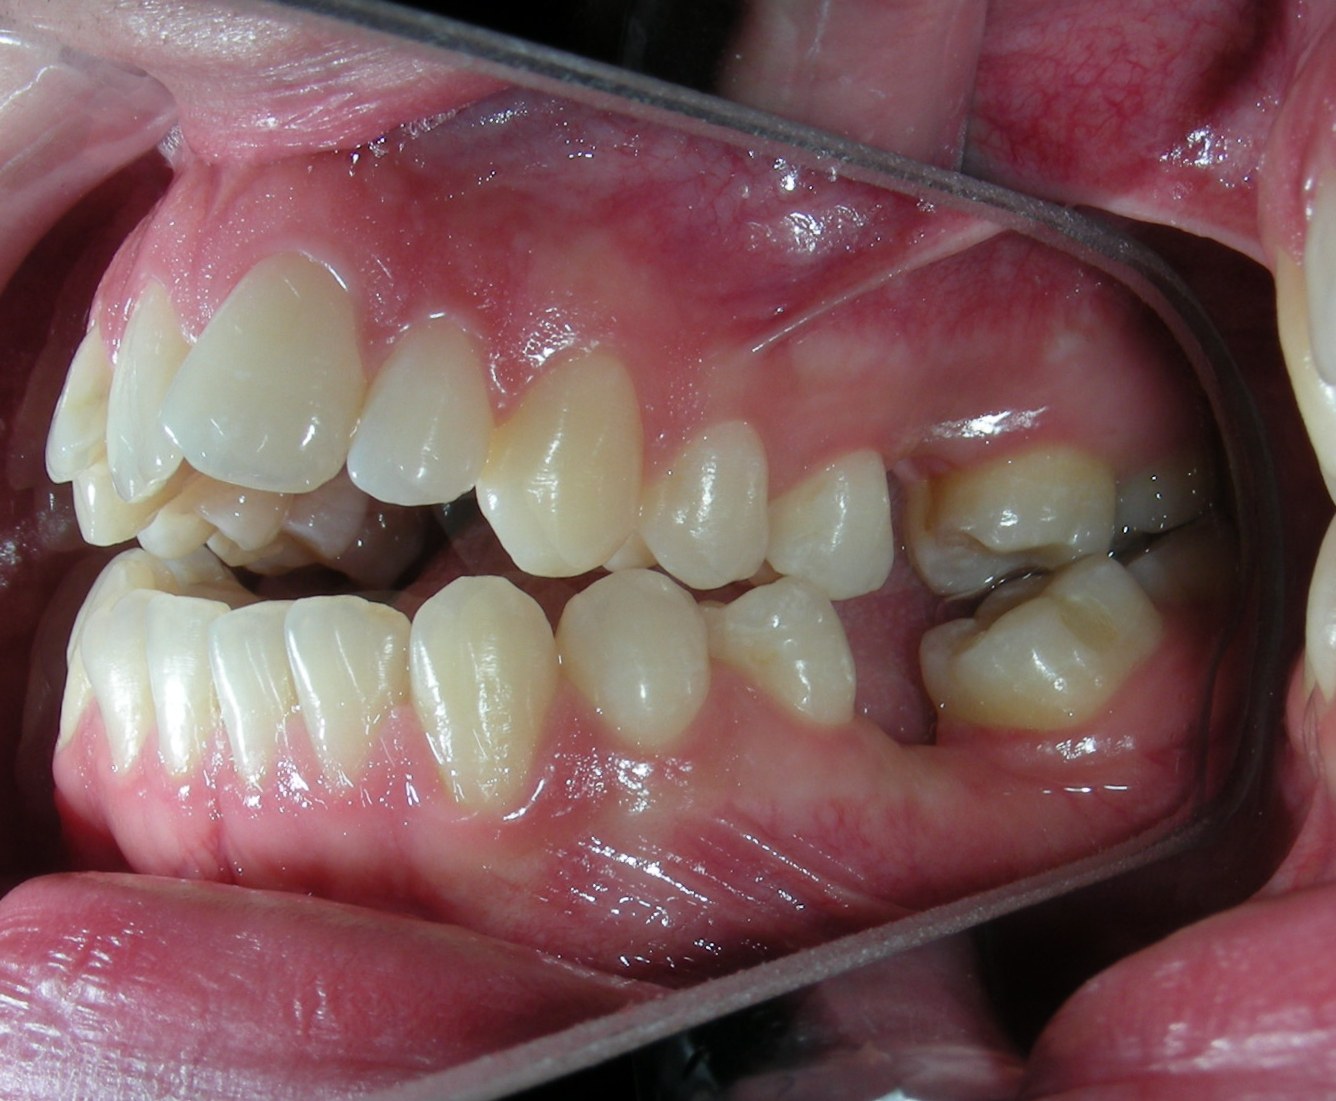

The patient presented with an anterior open bite, characterized by the absence of vertical overlap between the upper and lower incisors, and bilateral posterior crossbite. Extraoral examination revealed a vertically long facial pattern with an increased lower third of the face. The profile is convex with a retruded chin, indicating sagittal and vertical skeletal imbalances. We find also the inclined bipupillary line, which corresponds to facial asymmetries and altered occlusal plane.

Intraoral Examination:

Absent #16, #36 and #46 , No Angle molar relationship . Projection of canines axes in class II relationship . Anterior open bite: Over Bite – 8 mm). Bilateral posterior crossbite: Involvement of upper posterior sectors with inverted buccal-lingual relationship. Moderate Crowding at the level of the upper and lower incisors. Acceptable Oral Hygiene with no periodontal issues